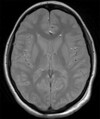

Whaty type of image is this?

A Proton Density Image